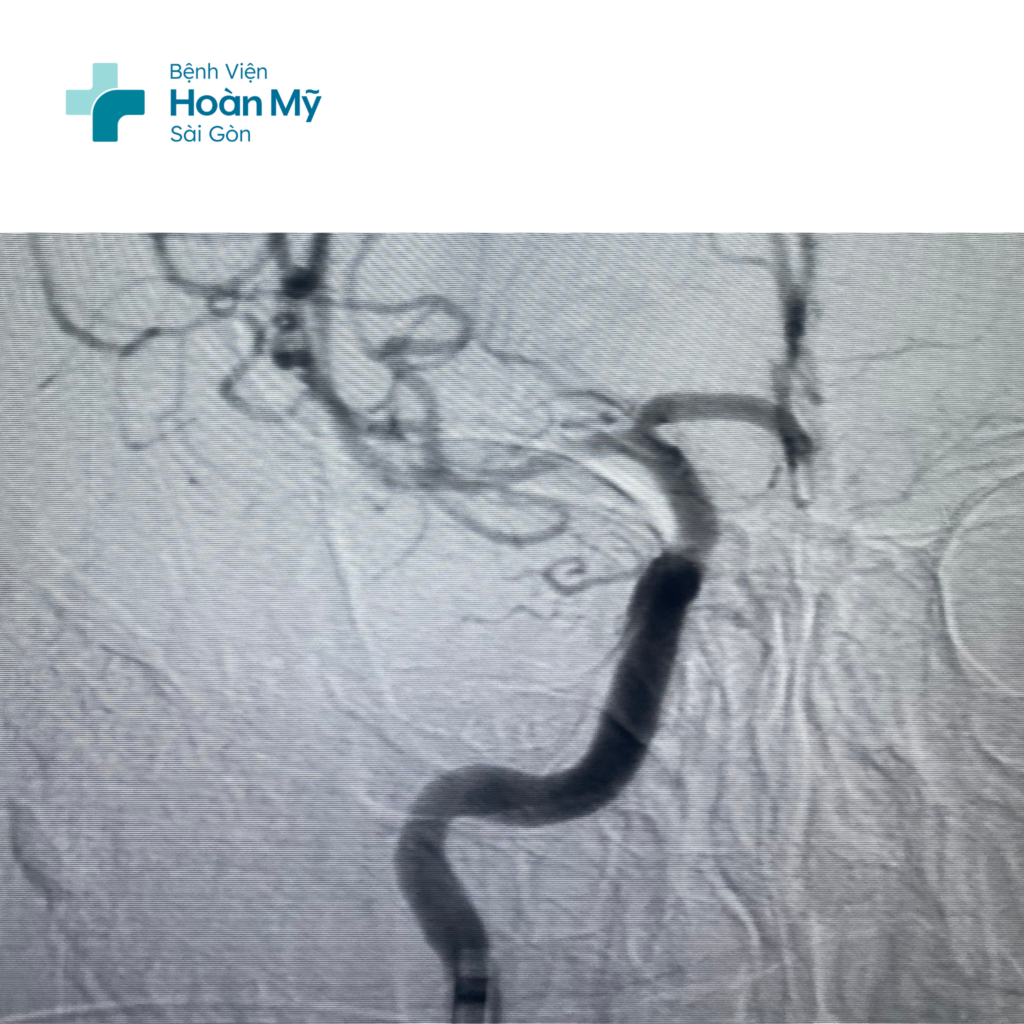

Hình ảnh CT mạch máu não trước can thiệp: Tắc hoàn toàn ĐM cảnh trong và não giữa phải

Hình ảnh ĐM cảnh trong và não giữa phải trước (trái) và sau khi can thiệp (phải)